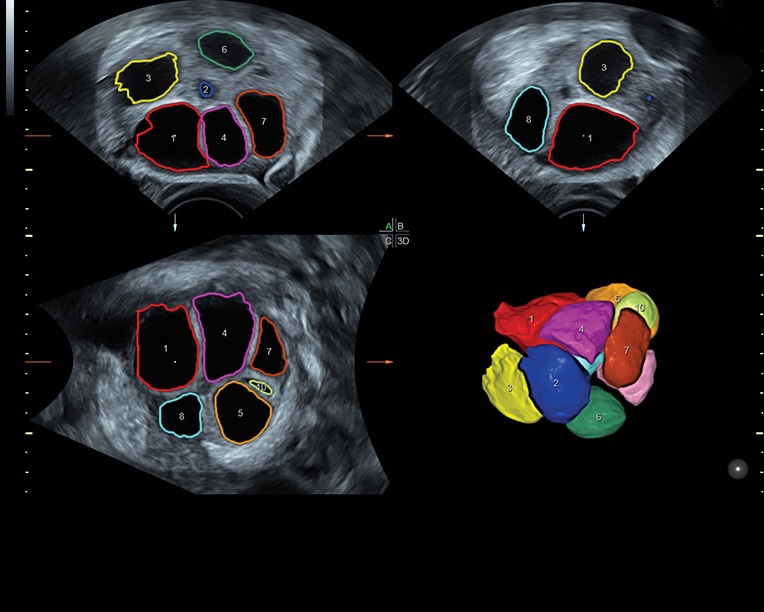

Ультразвуковая платформа Voluson S8 представляет собой оборудование экспертного класса с передовыми возможностями и высоким уровнем автоматизации процессов. Она позволяет проводить сканирование в режимах 2D, 3D и 4D с высоким качеством изображений.

Аппарат Voluson S8 базируется на надежной платформе VCA, которая имеет множество положительных отзывов. Она обладает высококонтрастной технологией объемной реконструкции, обеспечивая качественное воспроизведение изображений. Информация выводится на широкоформатный цветной монитор размером 23 дюйма для убедительной демонстрации плода будущим родителям и облегчения работы врача.

Система предназначена как для коммерческой, так и для государственной медицины, в клиниках с высокой загруженностью пациентами. Voluson S8 отлично справляется с большим объемом работы благодаря шаблонизированным отчетам и автоматизации обработки и постановки диагнозов с помощью функций SonoNT, SonoVCAD, SonoAVC и STIC. Это делает аппарат коммерчески выгодным и окупаемым в ближайшей перспективе.

• Сложные инструменты для оценки качества плода: Сканер оснащен инновационными инструментами, позволяющими проводить детальную оценку состояния плода, включая его сердечную деятельность, анатомию и кровоток.

Технологии, доступные на ультразвуковом сканере Voluson S8:

• Технология SonoRenderlive: Эта технология облегчает получение 3D/4D изображений путем автоматического изменения положения плоскости визуализации в зависимости от движений плода. Она позволяет получить реалистичные и объемные изображения, что полезно для демонстрации плода будущим родителям и для дополнительного анализа.

• Программа для исследований сердца плода с возможностью цветовых допплеровских и ангиографических исследований на основе анализа пространственно-временной корреляции изображений (STIС)

• Программное обеспечение для исследования сердца плода в режиме 3D/4D (быстрый доступ к плоскостям сканирования) по рекомендациям ISUOG